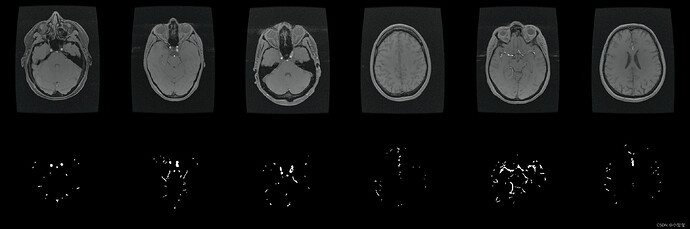

整个流程的演示我以医疗应用为背景,基于UNet完成训练、量化、部署整个流程。PS:之前想以细胞分割来展示,但是GT视觉效果比较密恐,所以找师弟要了一套看来舒服一点的医疗数据集重新训练更换效果图。

- 数据集来自2022年发表在TMI的论文《Attention-Assisted Adversarial Model for Cerebrovascular Segmentation in 3D TOF-MRA Volumes》。数据集实际上是MRA图像,我这里只保留了脑血管GT,用二分类的Unet来介绍整体的部署流程(这里感谢诺师弟的帮助)。

执行完代码之后,得到ONNX结果,看起来没啥问题,可以进行阶段2的相关数据转换了。